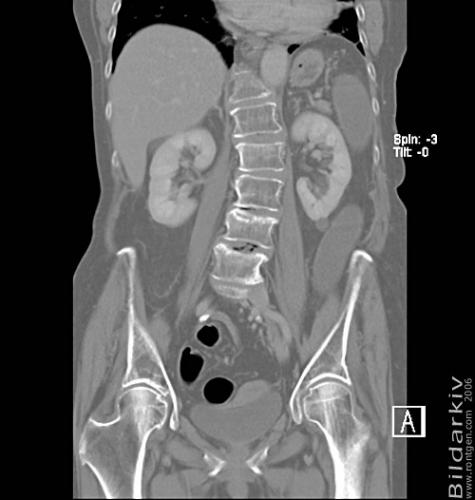

CT colon 31

Datortomografi av tjocktarmen (colon) med infunderad luft i tarmen samt med kontrast i blodbanan. Koronar bildserie.

CT multislice 16